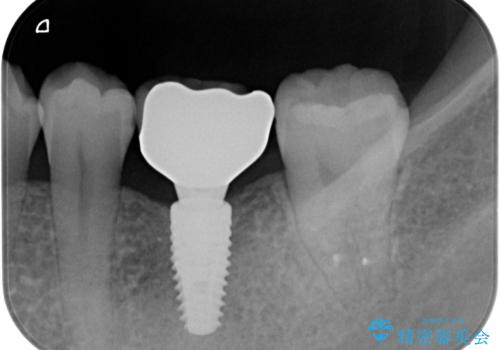

- 左下大臼歯が噛みしめにより割れてしまい、抜去後のインプラント治療を希望され来院されました。

しっかりと咬合負担能力の増えるインプラントによる欠損補綴を計画します。

ブリッジのように前後の歯を削ることなくしっかりと咬合機能の回復を行うことができました。